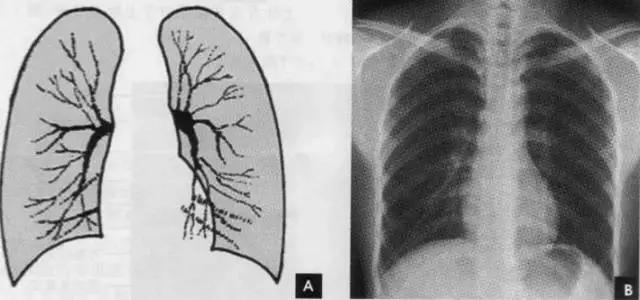

2、肺纹理

肺纹理为自肺门向肺野呈放射状分布的树枝状阴影,它主要是肺动脉的投影,肺静脉、支气管和淋巴管也参与形成。肺纹理由肺门向外围延伸,逐渐变细,至肺野外带渐细小而稀少,距侧胸壁内缘约1cm范围内的肺野基本无肺纹理可见(图下图)。